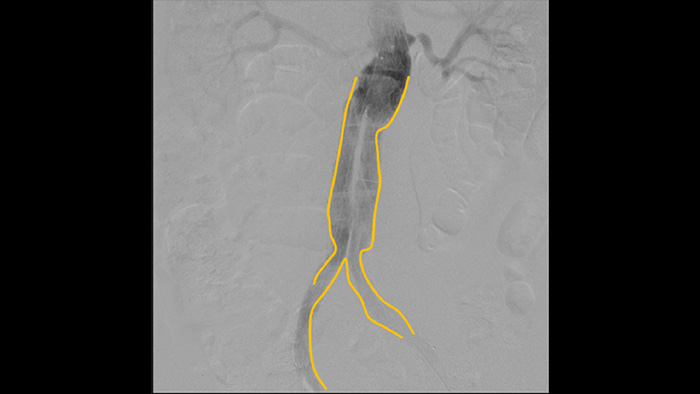

Utilice la herramienta de creación de contornos para marcar fácilmente una bifurcación o rama lateral simplemente dibujando en el monitor de la estación de visualización móvil con el dedo o un ratón conectado externamente.

La angiografía por sustracción digital (DSA) se utiliza en procedimientos vasculares intervencionistas para visualizar claramente los vasos sanguíneos mediante la eliminación de estructuras que puedan oscurecer la visibilidad de los vasos. La fluoroscopia Roadmap superpone una imagen de contraste sustraída previamente adquirida en la fluoroscopia en tiempo real, lo que le permite rastrear un dispositivo sin volver a inyectar el contraste.